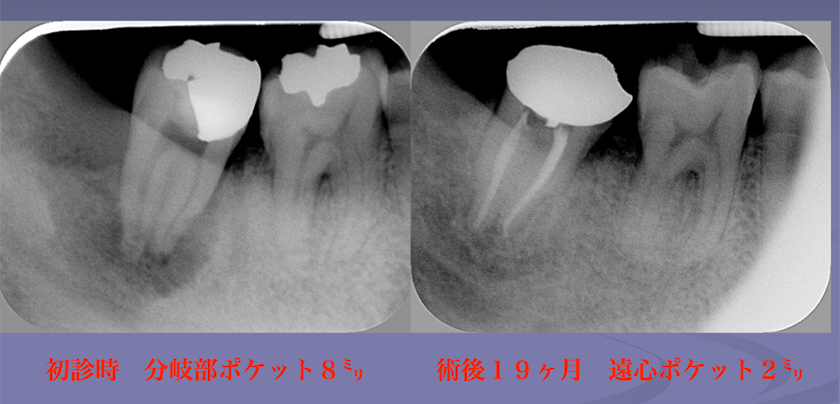

エンド・ペリオ病変

LIVE配信 2026年7月22日(水) 19:30~21:00

見逃し配信:2026年7月29日(水)~8月7日(金)

講演のポイント

・エンド・ペリオ病変の病態を理解する

・エンド・ペリオ病変の治療介入のタイミングについて理解する

・臨床におけるエンド・ペリオ病変の取り扱いや意思決定における重要事項を知る